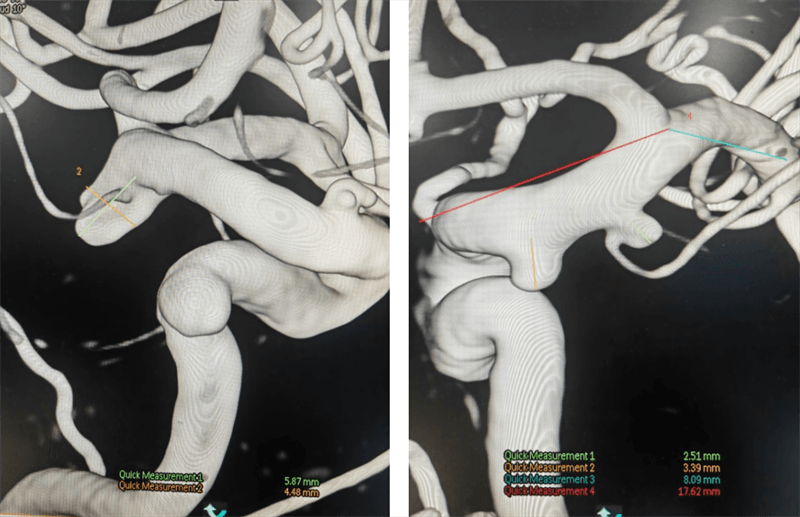

(術(shù)前3D造影)

術(shù)中,介入團隊對患者右側(cè)頸內(nèi)動脈末端兩枚動脈瘤采用密網(wǎng)支架覆蓋,左側(cè)脈內(nèi)動脈末端動脈瘤采用彈簧圈填塞。在手術(shù)過程中,對患者左側(cè)頸內(nèi)動脈使用6F長鞘,6F中間導(dǎo)管建立通路 ,分別使用X17 與headway-17微導(dǎo)管輸送Atlas輔助支架和數(shù)枚彈簧圈完成填塞。右側(cè)頸內(nèi)動脈使用導(dǎo)引導(dǎo)管 GC-088-09 顱內(nèi)支撐導(dǎo)管同軸,在導(dǎo)絲引導(dǎo)下,將遠端通路導(dǎo)管DA6115ST至右側(cè)頸內(nèi)動脈海綿竇段。選擇合適工作角度,沿神經(jīng)血管導(dǎo)絲TNGW-14-200-S將TJMC18 Plus微導(dǎo)管送至大腦中動脈,沿TJMC18 Plus送入NUVA 4.5*25mm血流導(dǎo)向密網(wǎng)支架, 支架順利打開。支架釋放后造影可見支架顯影清晰,形態(tài)良好,無貼壁不良。支架釋放后觀察10分鐘,無異常。經(jīng)過幾個小時的奮戰(zhàn),手術(shù)終于順利結(jié)束,患者重獲健康。